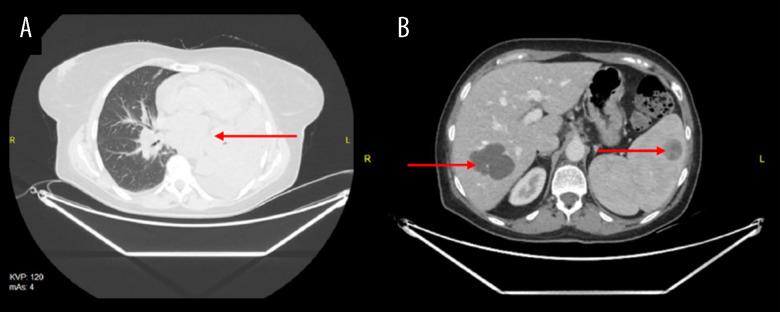

BACKGROUND Lung cancer is the most common malignant neoplasm diagnosed worldwide. Early diagnosis and treatment are of great importance for patient's prognosis. A wide variety of pulmonary conditions display clinical and radiological presentation similar to that of lung cancer, and the awareness of their existence can help in making correct diagnoses. CASE REPORT This article presents a description of 4 patients with an insidious type of lesions mimicking pulmonary carcinomas. The first patient was referred to Department with a tumor-like lesion in the right lung. After CT of the chest and core-needle biopsy, the lesion turned out to be an ectopic thyroid tissue. The second patient reported a dry cough and weight loss. A lung nodule mass was revealed in chest CT and the patient was diagnosed with pulmonary tuberculoma. The remaining 2 patients, despite the suspicion of lung cancer, were subsequently diagnosed with a post-traumatic pleural hematoma and diffuse large B cell lymphoma. CONCLUSIONS Low-dose computed tomography of the chest plays a significant role in the diagnosis of newly detected lesions in the lungs. However, due to the similarity of the image of cancer to that of other diseases, the ultimate diagnosis should be based on the interpretation of full imaging diagnostic tests, clinical presentation, and histopathological examination of the material obtained from the lesion. Analysis of cases enables us to expand our understanding of the diseases that need to be considered in differential diagnosis of a patient with a detected tumor-like lesion in the lungs.

本文介绍了 4 例类似肺癌的隐匿性病变患者。第 1 例患者因右肺内占位性病变就诊。胸部 CT 和经皮肺穿刺活检后,病变为异位甲状腺组织。第 2 例患者以干咳和体重减轻为主要表现,胸部 CT 显示肺部结节,诊断为肺结核球。其余 2 例患者尽管怀疑肺癌,但随后诊断为创伤性血胸和弥漫性大 B 细胞淋巴瘤。